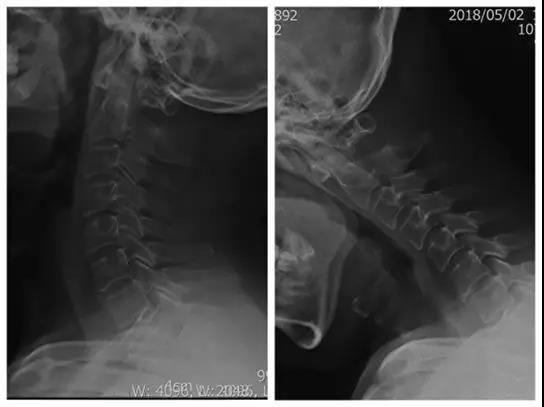

患者:男,35岁

主诉:外伤后肩颈部疼痛伴左上肢放射痛、麻木10天

现病史:患者因10天前从高处坠落致肩颈部疼痛,左上肢放射痛、麻木

左上肢胀痛、麻木,麻木感以示指、中指及环指指尖为著;

左侧肱二头肌肌腱反射减弱、左侧肱三头肌肌腱反射消失、左侧膝腱反射消失、双侧跟腱反射减弱;

左侧Hoffmann征弱阳性,其余病理征未引出;

四肢肌力未见异常。

诊断:颈椎病(C6/7)

术前X线正、侧位片